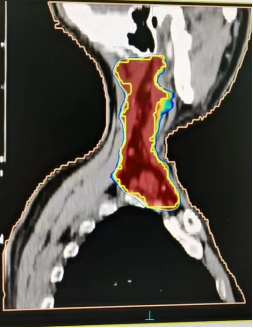

(五)食管癌

放射治疗半程对比